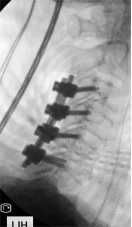

7. 复杂脊柱骨折内固定技术

随着区域内社会经济开发,复杂严重脊柱脊髓损伤病例增加,如何良好的手术治疗解除脊髓压迫、重建脊柱稳定性,使患者创伤最小、收益最大是促进患者康复至关重要的一环。我院已熟练开展各类脊柱损伤修复重建技术,每年完成复杂脊柱骨折手术处于区域领先水平。